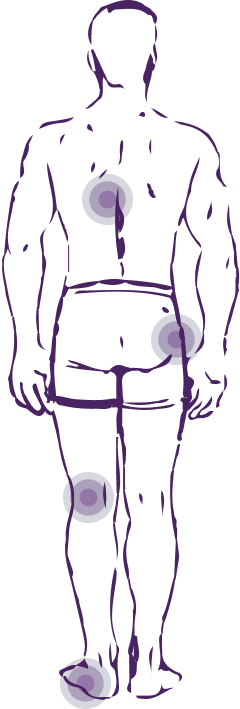

Симптоми вальгусу/варусу

Супроводжується різкими болями, що прострілюють, може початися оніміння і поколювання в нозі.